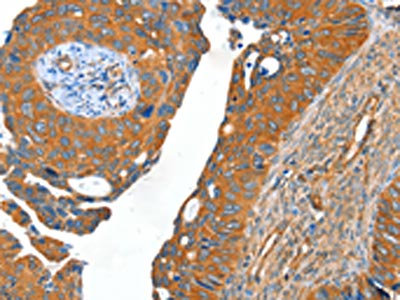

The image on the left is immunohistochemistry of paraffin-embedded Human cervical cancer tissue using CSB-PA998335(ACOT11 Antibody) at dilution 1/40, on the right is treated with fusion protein. (Original magnification: ×200)

The image on the left is immunohistochemistry of paraffin-embedded Human colon cancer tissue using CSB-PA998335(ACOT11 Antibody) at dilution 1/40, on the right is treated with fusion protein. (Original magnification: ×200)